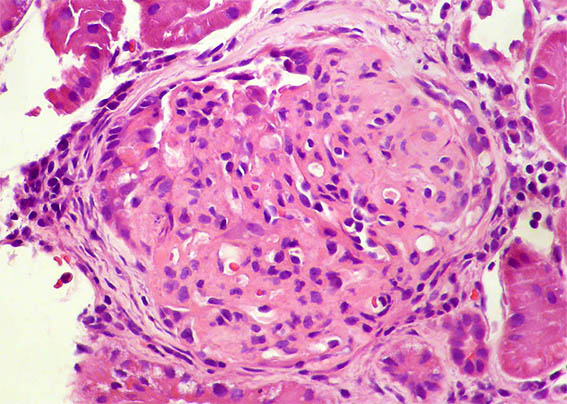

Se hace biopsia del injerto renal, observe las imágenes.

Figura 1. H&E, X100.

Figura 5. H&E, X400. Hipercelularidad endocapilar, exudativa, y una posible semiluna epitelial.